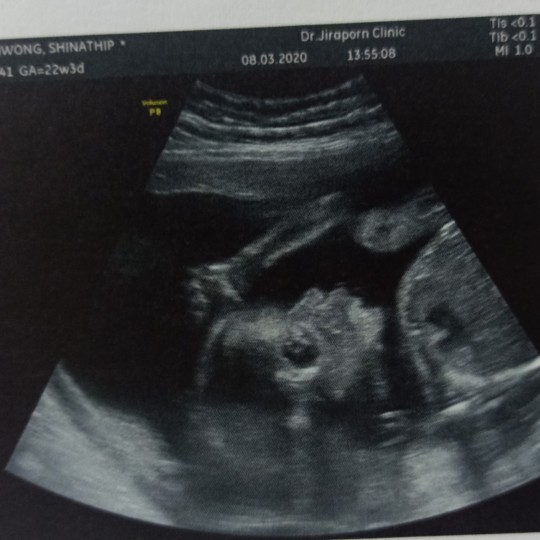

22 week ค่ะ